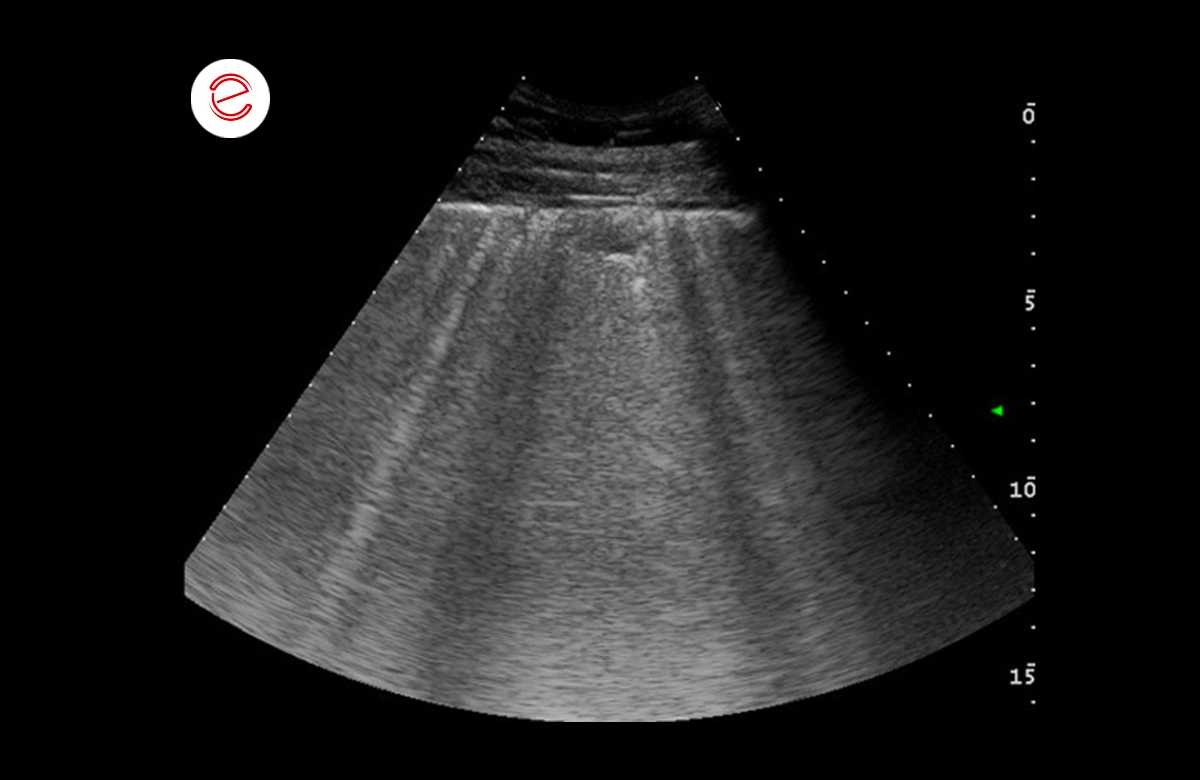

The images show numerous comet tail artefacts widespread on both the right and left side that are suggestive of pulmonary edema.